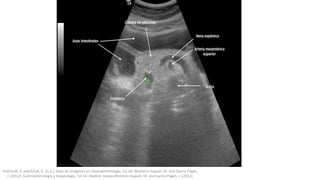

imagenEcografía abdominal

Prueba de elección para iniciar la investigación de un paciente

con sospecha de CDL, aunque sólo llegan a visualizarse en el

50% de los casos. Sin embargo, su sensibilidad para detectar la

dilatación del colédoco (superior a 6 mm en pacientes con

vesícula y a 8 mm en colecistectomizados) es de un 75%

aproximadamente.

-En individuos con cálculos biliares, ictericia y dolor biliar, un colédoco

dilatado en la ecografía sugiere con firmeza cálculos en el colédoco-